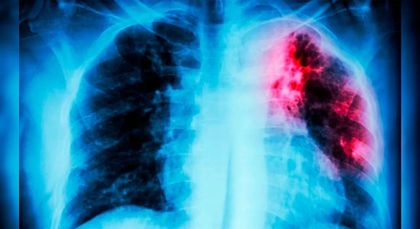

¿Crisis en la cárcel El Pedregal? Diez casos de tuberculosis y denuncias por presunta inseguridad alimentaria

Corte Constitucional ordenó medidas urgentes por riesgo sanitario en cárceles y centros transitorios de Medellín